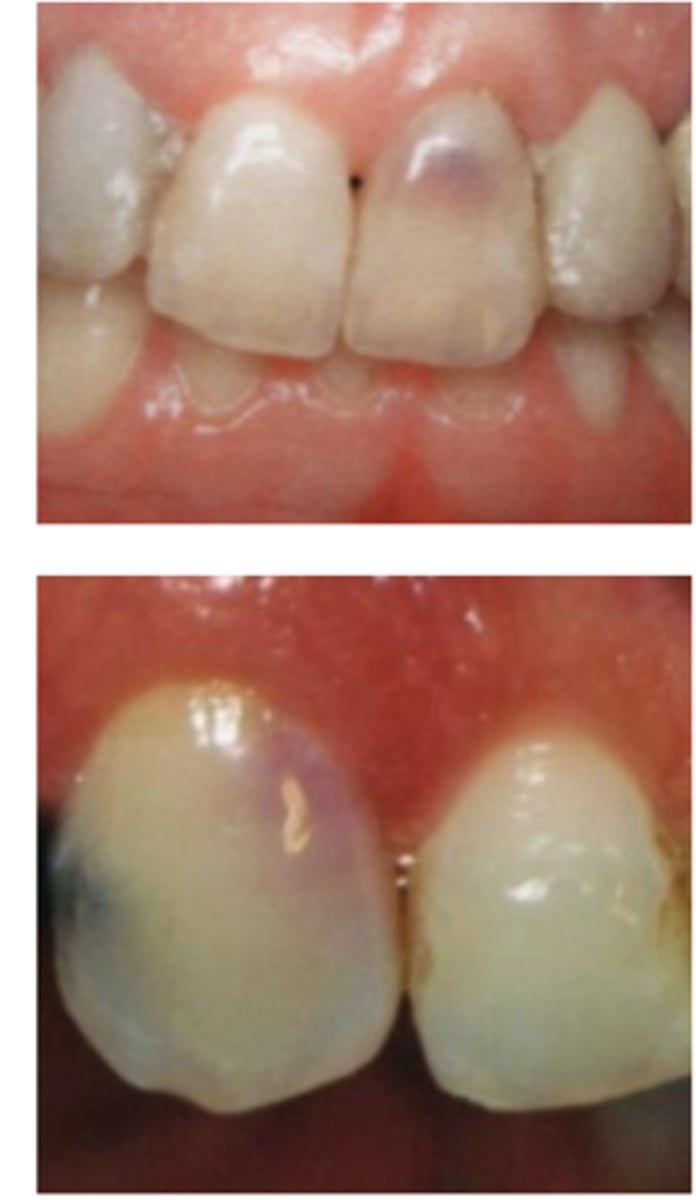

What is the diagnosis?

- Usually asymptomatic and have a normal appearance

- May have pink/red spot on the crown due to granulation tissue in the coronal dentin

- May display signs of pulpitis:

+ to sensibility tests in (partially) vital cases

- to sensibility tests in necrotic cases

Internal inflammatory resorption

- Symmetrical ballooning of root canal

- Lesion does not move when PA is taken from

different angles

- Usually does not have periapical lesion (Apical portion of root is vital!)

- Lesion may perforate into alveolar bone

- CBCT is recommended

Patient presents asymptomatic with a normal appearance but there is a pink/red spot on the tooth, what is the most likely diagnosis?

Patient presents with symmetrical ballooning of the root canal and lesion does not move when PA is taken from different angles. There is no PARL. What is the most likely diagnosis?